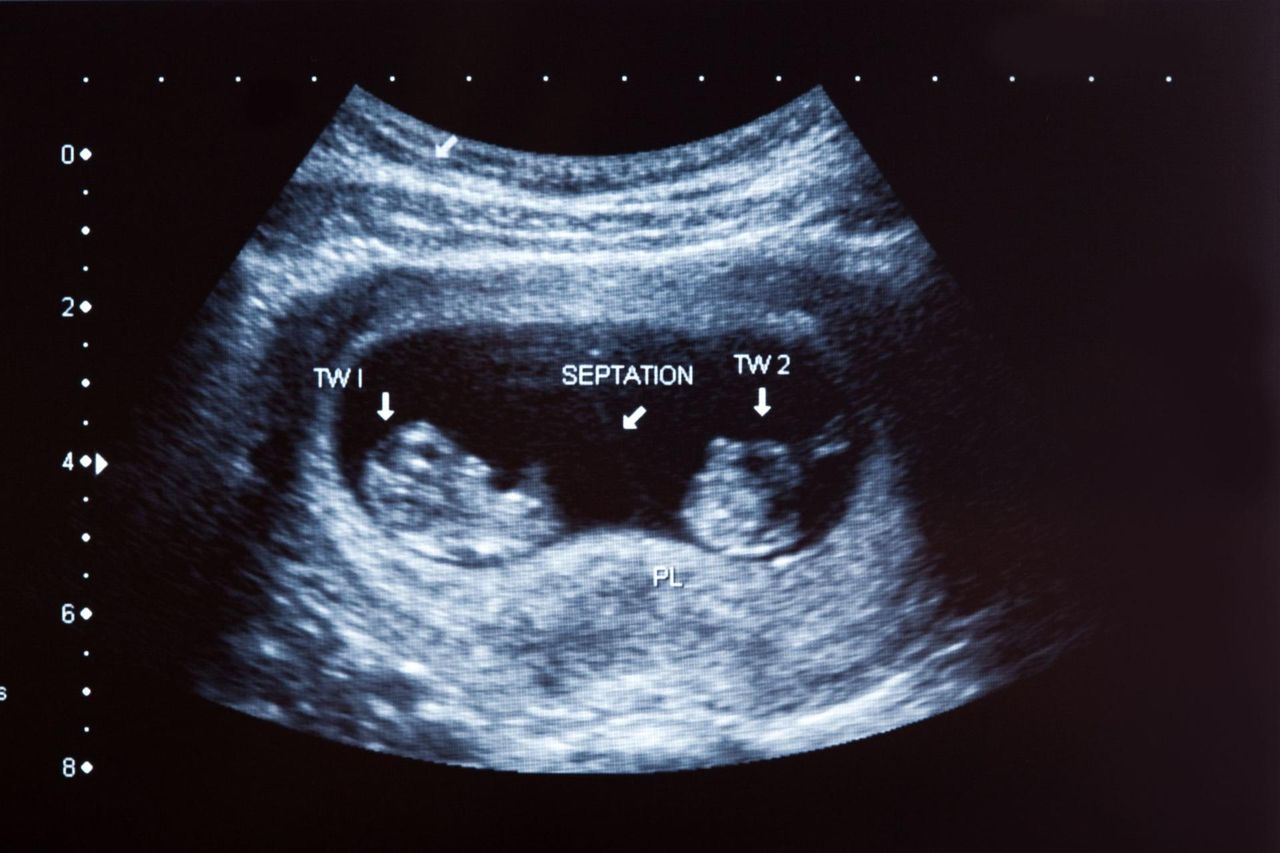

Sytuacja ta została opisana jako "fetus in fetu", co dosłownie oznacza "płód w płodzie". To rzadka anomalia, która polega na obecności płodokształtnej masy w ciele noworodka lub niemowlęcia. Jej przyczyną jest niepełne oddzielenie płodów.

Przypadek Hindusa był dla lekarzy szokujący, ponieważ płód w brzuchu Sanju był dużych rozmiarów. Ponadto prowadził pasożytniczy tryb, ponieważ żywił się tym, co jadł mężczyzna. Z tego powodu Sanju - pomimo tak dużego brzucha - był chudy i niedożywiony. Usunięcie pozostałości po jego bliźniaku uratowało mu więc życie.